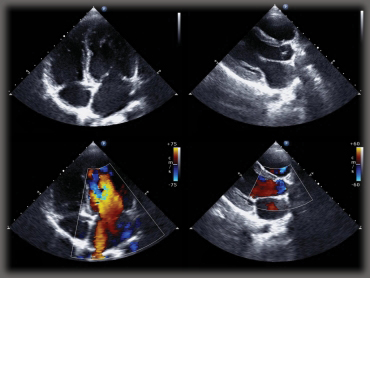

Right ventricular (RV) dysfunction is a characteristic of several disorders such as pulmonary hypertension, congenital heart disease and cardiomyopathy, making RV function evaluation key to effective prognosis and diagnostic value in such disorders. However, diagnosis through RV function is challenging due to anatomical configuration of the RV. Right ventricular outflow tract (RVOT) is an important measurement of overall RV function. In a new study, researchers in the Department of Pediatrics at Tokushima University evaluated if measurement of pulmonary annular motion velocity could be a reliable and useful tool to determine right ventricular outflow tract (RVOT) performance in pediatric patients with RV dysfunction. The research paper, entitled “Pulmonary Annular Motion Velocity Assessed Using Doppler Tissue Imaging – Novel Echocardiographic Evaluation of Right Ventricular Outflow Tract Function” was published in Circulation Journal.